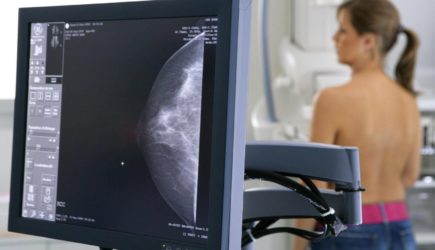

Маммография: почему врачи назначают её женщинам именно после 40 лет Маммография: почему врачи назначают её женщинам именно после 40 лет

Пожалуй, каждая женщина знает о том, что, стоит ей преодолеть 40-калетний порог, как врач тут же порекомендует пройти процедуру под названием маммография. С тех самых пор маммографию необходимо будет делать ежегодно, а после 50-ти и 2 раза в год. Почему же это обследование назначают только в данном возрасте?

Это обследование молочной железы посредством специального рентген-аппарата, который и называется маммограф. Во время процедуры врач-рентгенолог делает несколько снимков груди пациентки с разных ракурсов: сбоку и сверху. Для того, чтобы изображения получились качественными и четкими, молочные железы сжимаются специальными прозрачными пластинами. Подобные манипуляции существенно облегчают постановку правильного диагноза, а также позволяют уменьшить дозу радиации, которую, пусть и без того совсем небольшую (0,1–0,2 Рад), все-таки получают женщины во время маммографического исследования.

Американское онкологическое общество рекомендует женщинам в возрасте от 40 лет и в обязательном порядке старше делать маммограмму 1-2 раза в 2 года. Маммография по праву считается самым эффективным методом выявления патологий молочных желез. Ричард Уондер, председатель американской ассоциации онкологов ( ACS ) считает, что на основании проведенных исследований можно смело заявить, что маммография снижает смертность от рака молочной железы на 15% среди 40-50-летних женщин и на 20% среди тех, кому за 50. Поэтому именно это обследование рекомендуют всем женщинам, достигшим указанного возраста и в связи с этим попадающим в группу риска.